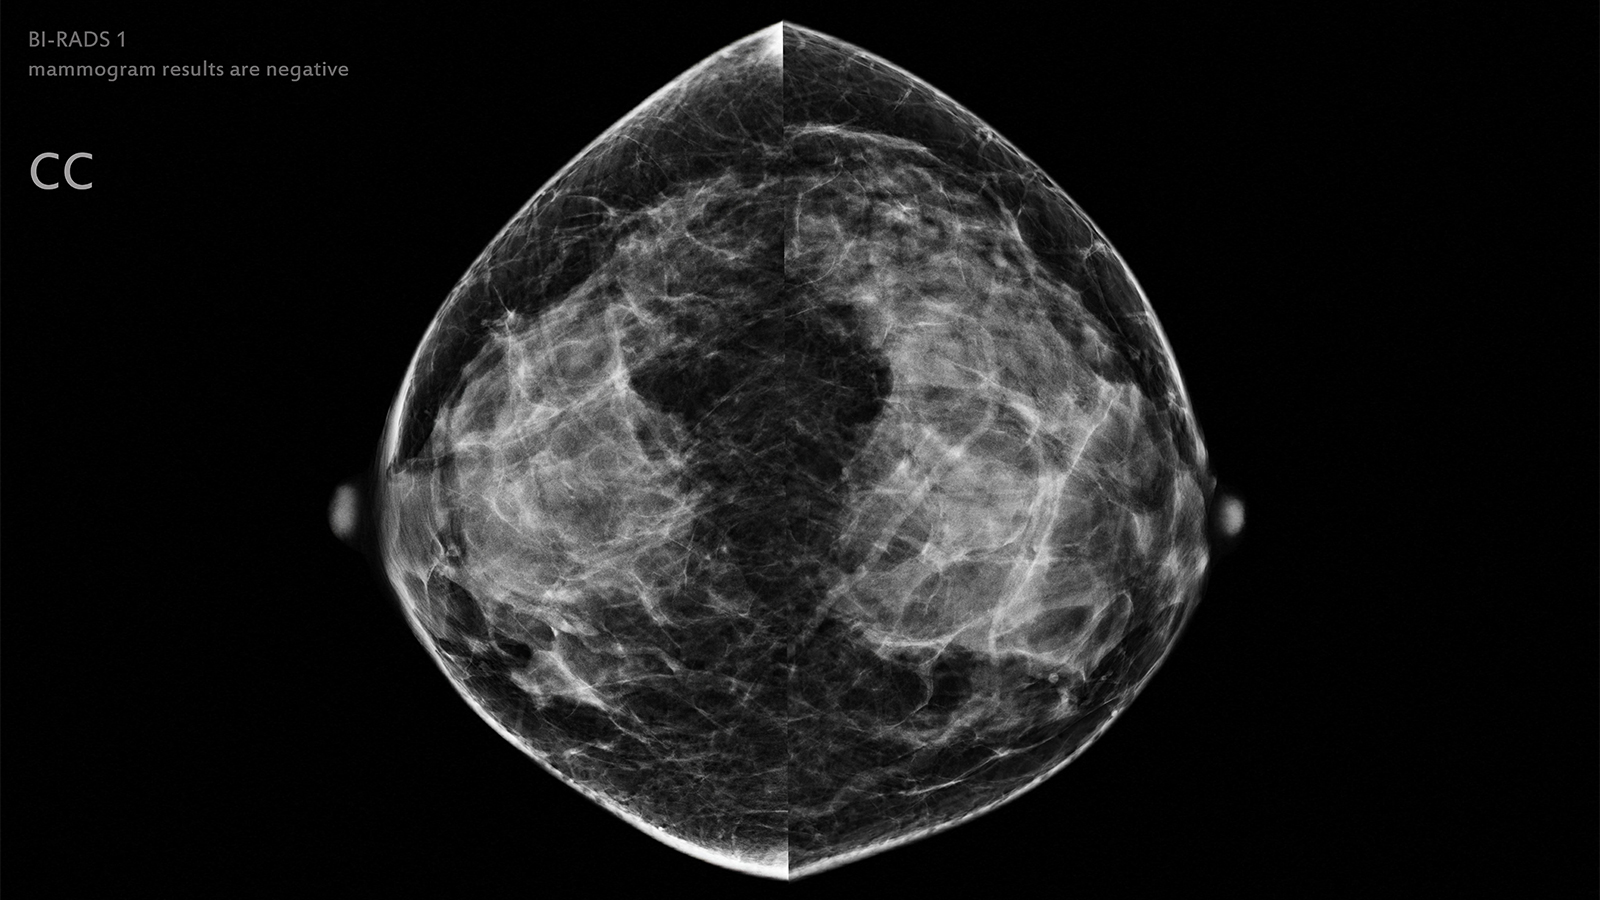

(MedPage Today) — Artificial intelligence (AI) could potentially be used to safely exclude low-risk mammograms from radiologist review, according to results from a prospective noninferiority trial.